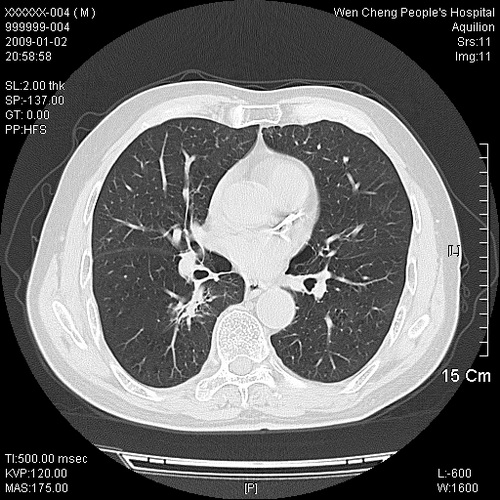

男性,73岁,有慢支病史,肿瘤系列标志物检验正常,血沉及血常规正常

右肺下叶背段小片状 磨玻璃样模糊影,内见血管及含气支气管像,支气管管壁增厚。考虑:慢性炎症!

支气管炎,小叶气肿,右下肺局限性炎症并轻度支气管扩张冠脉钙化。

右肺下叶背段小片状 实性与磨玻璃样影,内见血管及含气支气管像,支气管管壁增厚,边缘见长毛刺影。考虑:慢性炎症或肿瘤!建议抗炎治疗复查,密切观察随访!

右肺下叶片团状影内见扩张的含气支气管和支气管管壁增厚,其周有磨玻璃样模糊影和长毛刺。考虑慢性炎症可能性大。

2、右肺下叶片团状影内见扩张的含气支气管和支气管管壁增厚,其周有磨玻璃样模糊影和长毛刺。考虑周围型肺ca可能,结核不排。